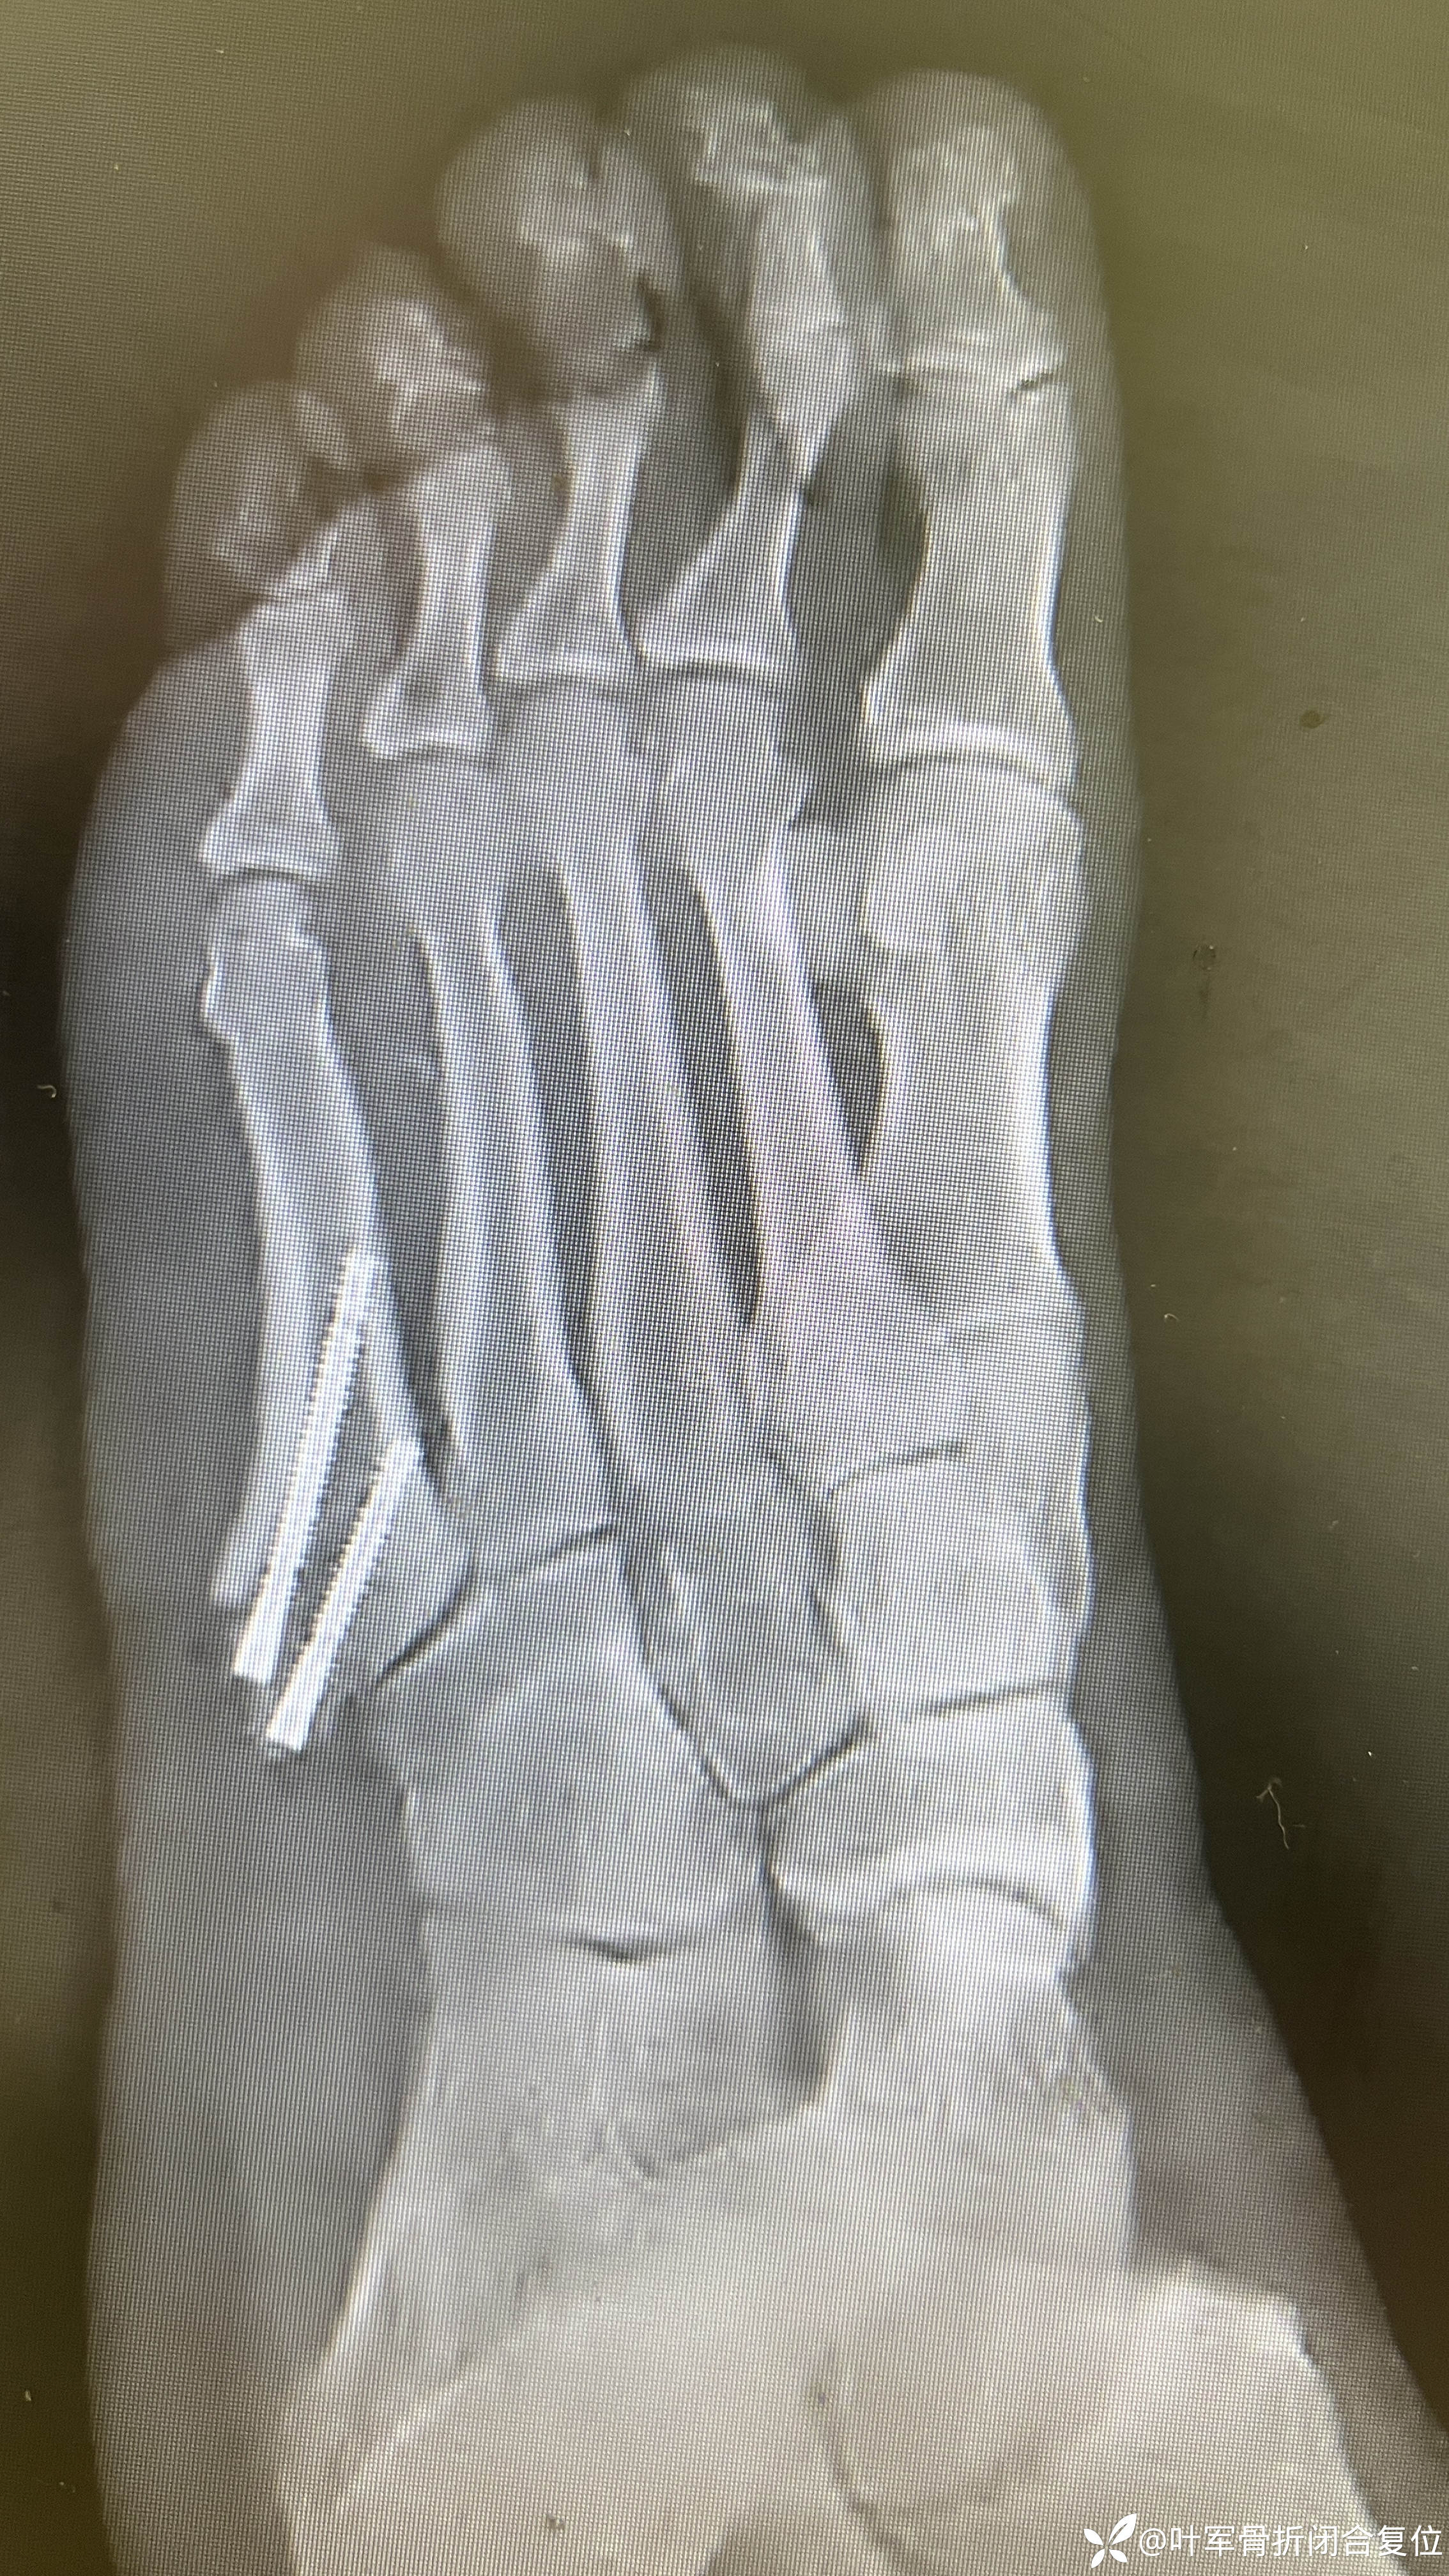

X线检查

分析处理

第五跖骨基底部骨折,是一种常见的足部损伤,尤其是在运动员和年轻人中更为常见。这种骨折通常是由于脚踝外翻或内翻导致的牵拉作用引起的。以下是关于第五跖骨基底部骨折的详细讲解,包括解剖、血供及治疗方法。

Torg 解剖分类

Zone 1:PseudoJones Fracture

近端结节撕脱

由于长跖韧带、足底筋膜外侧带或腓骨短肌收缩引起

可能延伸至骰跖关节

不愈合罕见

Zone 2:Jones Fracture

干-骺端连接处

涉及第四、五跖骨关节

血管分水岭区域

急性损伤

不愈合风险增加(15-30%)

Zone 3:Proximal Diaphyseal Fracture

位于第四、五跖骨关节远端

运动员中的应力性骨折

与高弓足畸形或感觉神经病变相关

不愈合风险增加

Torg X光分类

Type I:急性,窄骨折线,无髓内硬化

Type II:延迟愈合,骨折线扩大,伴髓内硬化。

Type III:不愈合,髓腔宽,无骨痂形成。